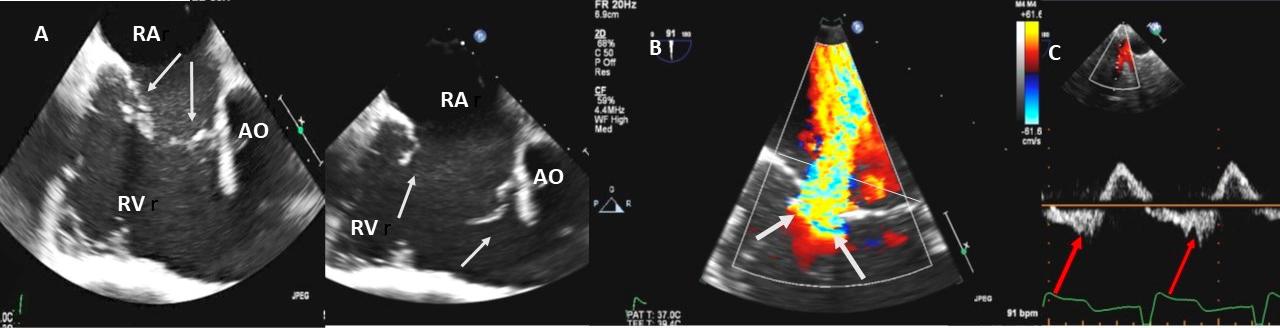

Examples of valvular injury directly from implantable cardioverter-defibrillator lead placement (Fig. 5A–C) or a permanent pacemaker (Fig. 6A–C) or endomyocardial biopsy in cardiac transplant recipients (Fig. 7A,B) are shown.

Fig. 5.Tricuspid regurgitation induced by pacemaker lead impingement. (A) 3D transthoracic echo showing and dilated RV, RA and anterior leaflet impingement by the device lead (red arrows). (B) Inspiratory systolic hepatic flow reversal (red arrows), which suggests severe TR. (C) Apical four chamber view showed severe tricuspid regurgitation. RA, right atrium; RV, right ventricle; AV, aortic valve; AL, anterior leaflet; PL, posterior leaflet; SL, septal leaflet; MV, mitral valve.

Fig. 6.Tricuspid regurgitation induced by pacemaker lead valve perforation. (A) Transthoracic 2D 4 chamber view showing pacemaker lead going through the TV leaflet (white arrow) and causing TR. (B) 3D enface view of the TV from the right atrial perspective showing the pacemaker lead going through the margin of the septal leaflet (SL) of the TV (white arrow). (C) 3D color Doppler view of the TV from the atrial perspective showing origin of TR at the site of leaflet perforation. MV, mitral valve; AV, aortic valve; PL, posterior leaflet; AL, anterior leaflet

Fig. 7.Tricuspid regurgitation following endomyocardial biopsy. (A) Flail tricuspid valve leaflet that occurred as a complication of an endomyocardial biopsy. Apical 4 chamber view showed flail septal leaflet (SL, septal leaflet; AL, anterior leaflet). (B) Color-flow Doppler imaging. Eccentric, anteriorly directed jet of tricuspid regurgitation (SL, septal leaflet of tricuspid valve; AL, anterior leaflet of tricuspid valve).